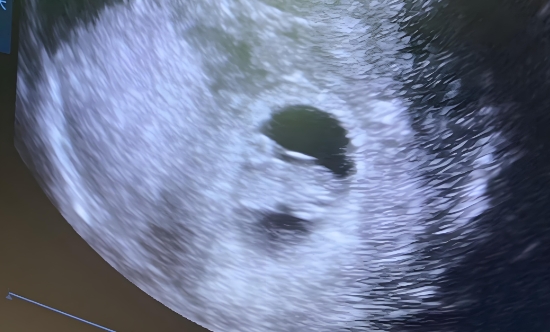

出现子宫内积液时,妇女需要立即去医院就诊,以便及时进行检查和治疗,以避免可能出现的并发症。在检查中,可以通过B超来检查积液的位置和数量,以确定诊断和治疗方案。